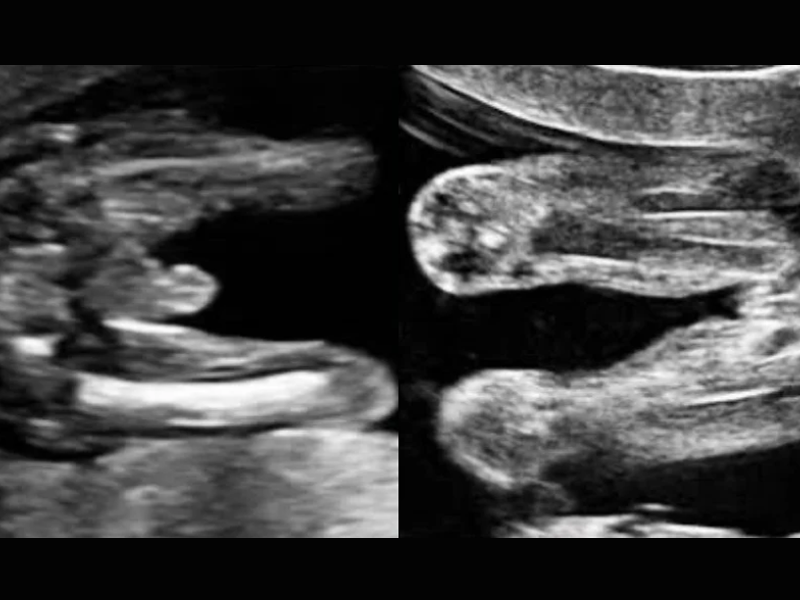

- Experience your baby’s movements in 2D